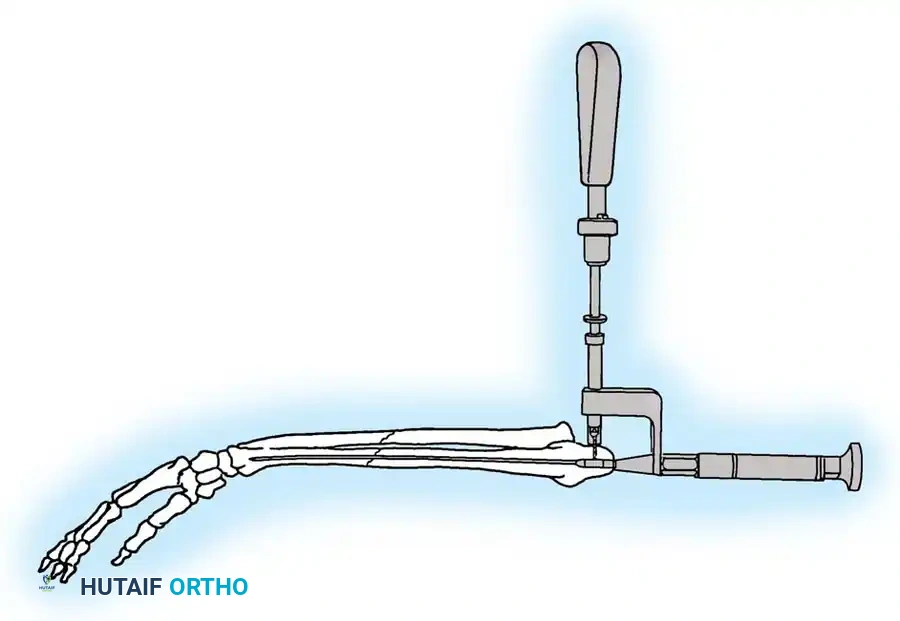

2. Intramedullary Fixation with Tension Band

If the fracture is more distal, or if there is a tendency for the proximal fragment to angulate posteriorly, a simple tension band wire is insufficiently stable. In these cases, intramedullary fixation (using Kirschner wires or a large cancellous screw) is combined with the tension band.

Kirschner Wires vs. Cancellous Screws:

* K-wires: The AO technique utilizes two parallel K-wires (1.6 mm or 2.0 mm) driven down the medullary canal. To prevent proximal migration, the K-wires must engage the anterior cortex of the ulna distal to the coronoid.

* Cancellous Screw: A biomechanical analysis by Murphy et al. demonstrated that a long 6.5-mm or 7.3-mm AO cancellous screw combined with a figure-of-eight wire provides a significantly stronger construct than K-wires. The screw must be long enough to achieve secure purchase in the ulnar diaphysis.

Fig. 54-55 Olecranon fracture repaired with long 6.5-mm AO cancellous screw and figure-of-eight tension band wire loop. Screw must engage cortex of diaphysis of ulna.

🔪 Surgical Technique: K-Wire and Tension Band (AO Technique)

- Reduction: Anatomically reduce the fragments and hold them temporarily with a reduction clamp.

- K-Wire Insertion: Introduce two parallel K-wires longitudinally from the tip of the olecranon across the fracture site. Direct them slightly anteriorly so they engage the anterior ulnar cortex distal to the coronoid process.

- Wire Loop: Pass an 18-gauge wire through a transverse drill hole in the distal fragment. Cross the wire in a figure-of-eight fashion over the posterior surface.

- Proximal Capture: Pass the wire around the protruding proximal ends of the K-wires.

- Double Twist: Weber and Vasey suggest twisting both limbs of the figure-of-eight loop. This double-twist modification ensures uniform compression across the fracture site.

- Securing K-wires: Bend the proximal ends of the K-wires 180 degrees, cut them short, and tap the bent ends deep into the triceps insertion and proximal bone to prevent symptomatic hardware prominence and migration.

Fig. 54-56 A and B, Transverse olecranon fracture repaired with Kirschner wires and tension band technique. C, Double twist modification of wiring suggested by Weber and Vasey.

4. Plate Osteosynthesis

If comminution with bone loss prevents the use of a tension band compression technique—due to the risk of shortening the olecranon and narrowing the greater sigmoid notch—plate fixation is mandatory. Plating is also the gold standard for Monteggia fracture-dislocations, oblique fractures extending distally, and fractures involving the coronoid process.

Construct Design:

Hand-contoured reconstruction plates or modern, anatomically precontoured locking plates (e.g., Acumed, Synthes) provide rigid, stable fixation. The plate is applied to the posterior (tension) surface of the ulna.

🔪 Surgical Technique: Plate Fixation

- Reduction: Restore the articular block. Temporary K-wires can be used to hold comminuted articular fragments.

- Plate Application: Apply a precontoured olecranon plate to the posterior aspect of the proximal ulna. The proximal portion of the plate often wraps over the tip of the olecranon to capture the proximal fragment with multiple locking screws.

- Fixation: Secure the plate distally to the ulnar shaft using standard cortical or locking screws. If an oblique fracture line is present, a lag screw can be placed independently or through the plate to achieve interfragmentary compression.

- Bone Grafting: If significant metaphyseal void exists after elevating impacted articular fragments, autogenous cancellous bone graft or allograft should be packed into the defect prior to final plate tightening.